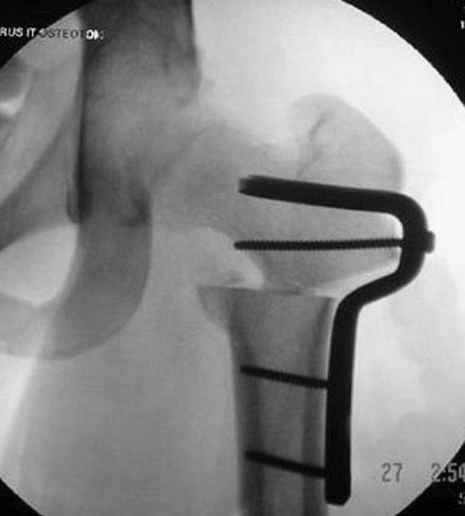

Несколько снимков из моей коллекции, чтобы разьяснить, почему мы до сих пор делаем различные варианты остеотомии.

На рисунке N1 предоперационный план лечения ложного сустава шейки бедра- линия ложного сустава, угол и направление введения импланта, клиновидная остеотомия в градусах и миллиметрах, второй снимок после коррекции, расчет, на сколько удлиняется конечность и размеры импланта;

N3 рисунок окончательный снимок, после операции моя рентгенограмма должен выглядеть примерно как эта картина. На N4 снимке клин перед удалением; N5 послеоперации 3 нед.; N6 окончательная рентгенограмма.

варус при проксимальном отделе 95 градусной пластиной.